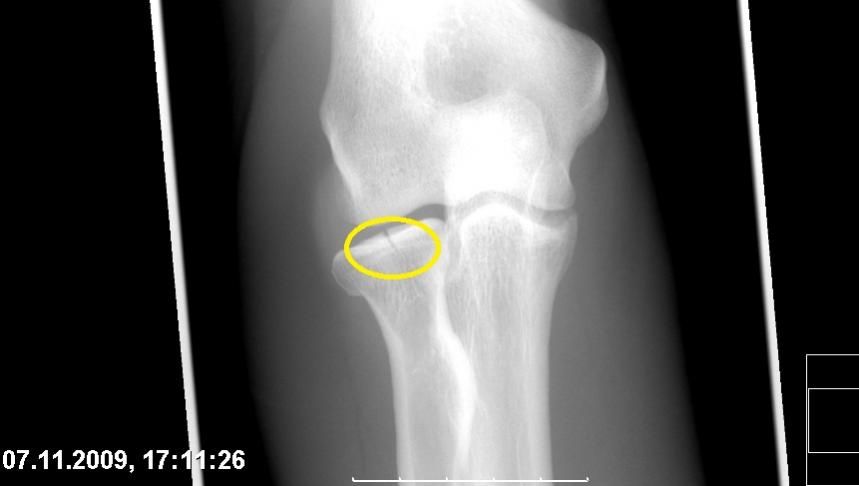

Also, am 11.9 war ja Termin beim Orthopäden. Dabei kam nach ca.2h Warten und nicht mal 10Min.Bla Bla beim Dok raus, das da noch ein Knochenstückchen im Gelenk rumwabert was bei wiederkehrenden Schmerzen raus muss.

Darin wird u.a. darüber berichtet, das Knochenabsprengungen/freie Gelenkkörper zu beschleunigter Arthrose führen könnten...

Links zum Glück nur das Speichenköpfchen, rechts eine Monteggia-Fraktur am Ellenbogen und zusätzlich auch noch das Handgelenk. Also eigentlich alles kaputt was nur irgendwie kaputtgehn kann, dass schaffen auch nur wenige (Docs meinten, beide Arme auf einmal wäre eher eine typische Inlineskater-Verletzung. Keine Ahnung wie ich genau auf die Straße aufgetroffen bin, hab da ein paar Sekunden Gedächtnislücke).

auch vorn übern Lenker + harte Landung = Radiusköpfchenfraktur im rechten Arm.